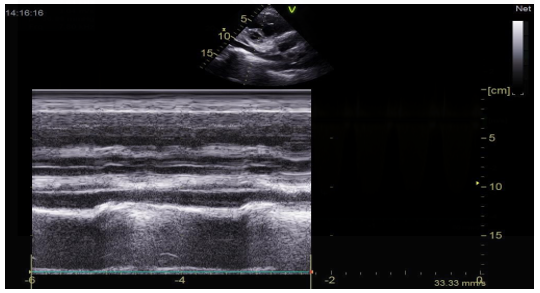

The transthoracic echocardiographic examination revealed (Figures 8 – 18):

- Left ventricule showed no sign of dilatation. Al though the assessment of contractile function was influeced by compressio from pulmonary hydatid cyst, it appears to maintain functionnality.

- The right ventricle exhibited no dilation (Figure 11) despite the presence of longitudinal systolicdys functio n (Figures 14).